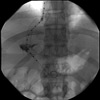

After puncturing the portal vein and placing a catheter, both the hepatic vein and portal vein are simultaneously injected. Virtually no flow through the liver from the portal vein is identified.